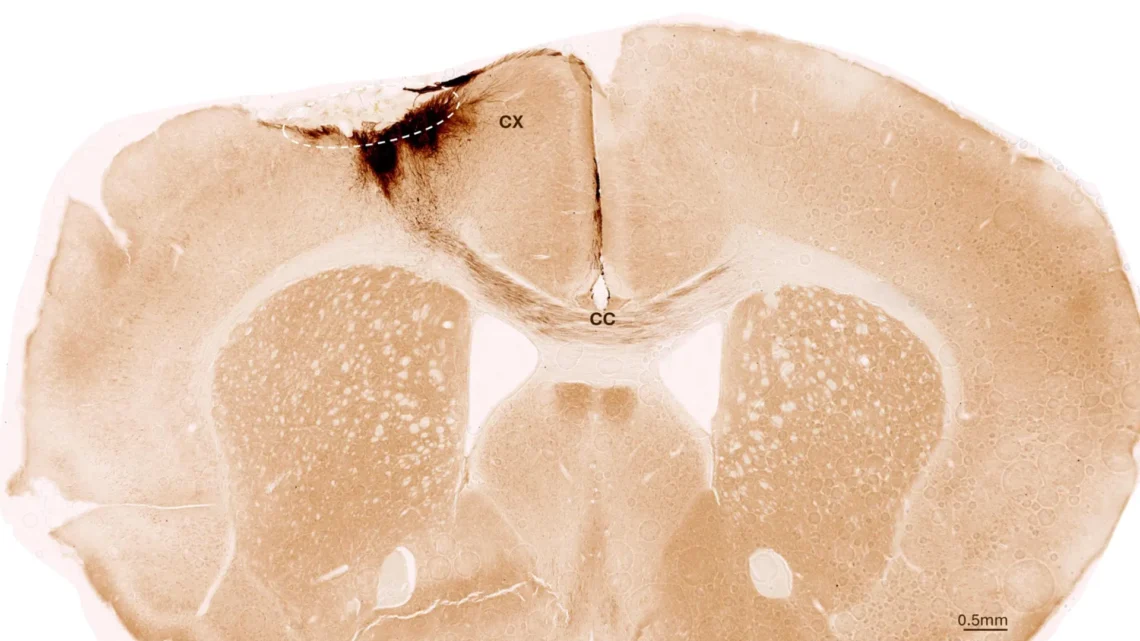

After one week, the team transplanted the neural stem cells into the damaged brain area. They employed various imaging and biochemical techniques to monitor the outcomes over five weeks. “We observed the survival of the transplanted stem cells and their transformation into functional neurons that communicated with existing brain cells,” Tackenberg explains.

The researchers identified additional markers of regeneration, including the formation of new blood vessels, a reduction in inflammatory responses, and enhanced integrity of the blood-brain barrier. “Our analysis exceeds the scope of other studies that primarily focused on immediate post-transplant effects,” Tackenberg states. Notably, stem cell transplantation in mice also mitigated motor impairments resulting from strokes, supported by an AI-assisted analysis of mouse gait.